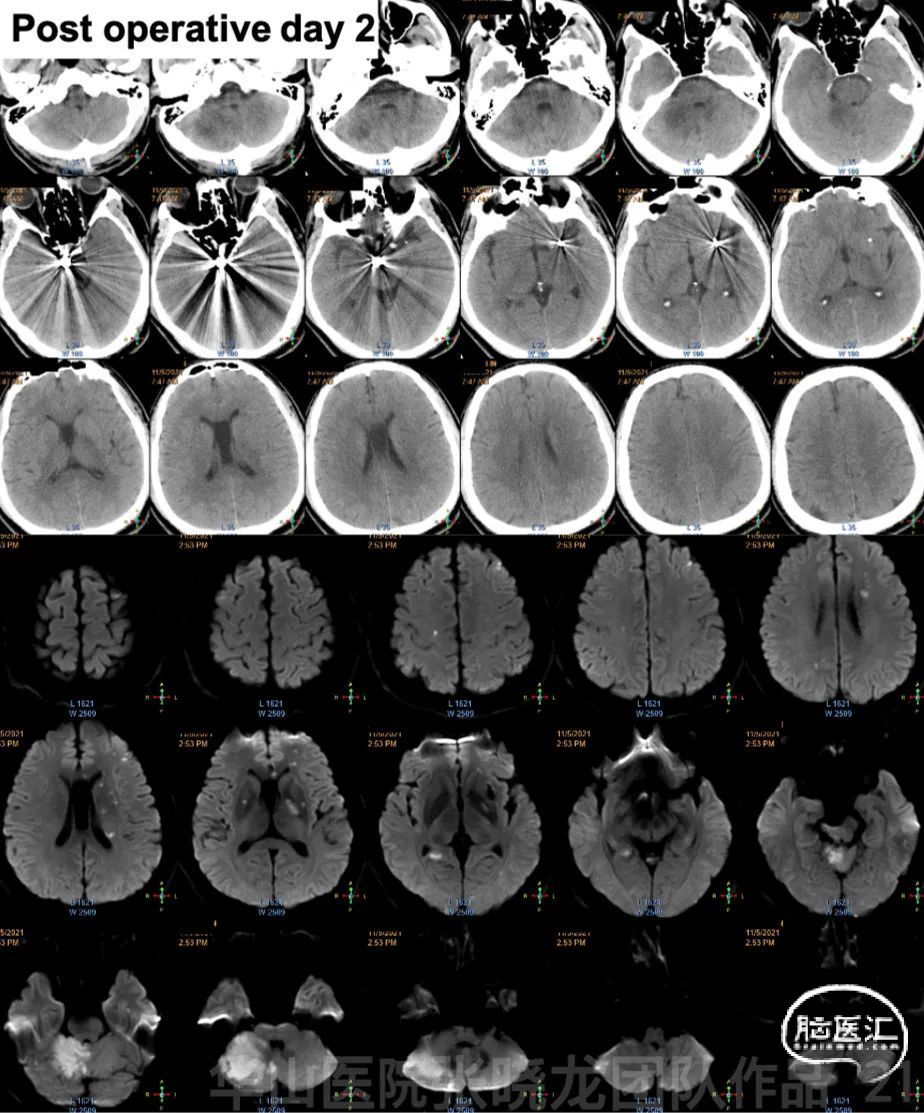

Figure 21. Post-operative day 2 head CT showed no hemorrhage and DWI depicted right cerebellum, midbrain and left basal ganglia region acute infarction with bilateral hemisphere scattered infarction.

图 21. 术后第2天头颅CT未见出血,DWI提示右侧小脑半球、中脑及左侧基底节区急性脑梗,双侧大脑半球散在梗死。

Post-operation to post-operative day 5:

1.Medication: Aspirin 100mg & Clopidogrel 75mg (AA 97.4%, ADP 98.3%).

Tirofiban 13ml/h maintained about 8 hours, changing to 15ml/h for 16 hours, 13ml/h for 4 hours, 10ml/h for 6 hours, 6ml/h for 38 hours.

2.PE: GCS 15, no nystagmus, left upper limb muscle strength IV+ and lower improved to V-, right Babinski (+) while left Babinski (-).